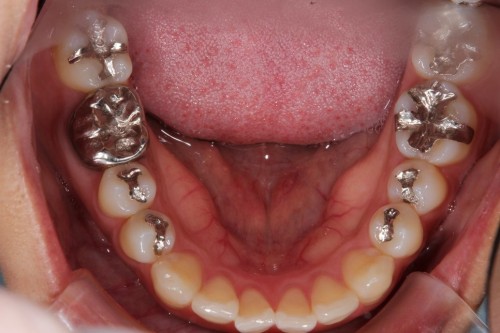

銀歯を白くするだけでずいぶんとイメージが変わります。

左右のダイレクトボンディング

費用5万円×4本

リスクとして欠ける可能性がある(修復可能)。